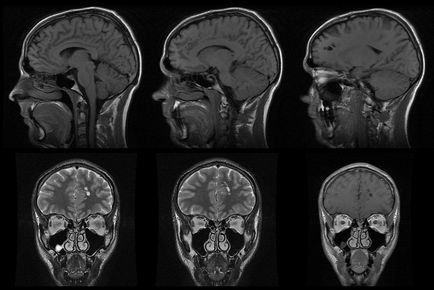

Hely és a városközpont közelében, a lakóhely vagy a munka - nem a fő paraméter. Először is, válasszon egy diagnosztikai központ, meg kell összpontosítani, amit berendezések telepítése a létesítményben. A legtöbb jó minőségű képeket, hogy MRI, megfelelnek az alábbi követelményeknek:

• magas területen, azaz nagy teljesítményű (1,5 Tesla).

3D-s számítógépes tomográfia nem ritkák most!

Hol az MRI a gerinc, a belső szerveket, vagy fej nélkül, gyorsan a sorok? A válasz nyilvánvaló - magánklinikák. Legtöbbjük modern berendezések és képzett radiológus kell tisztázni előre megismerjék hivatalos honlapján és a vélemények.